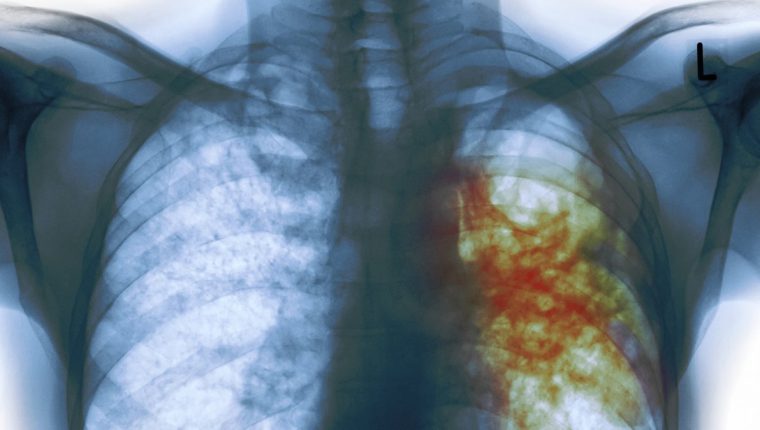

Día Mundial de la Tuberculosis: 10 datos que debe conocer sobre esta enfermedad

Qué es la tuberculosis latente que afecta a una de cada 4 personas

Según la OMS, el coronavirus pone en peligro los logros en la lucha contra la tuberculosis

Tuberculosis: la nueva cura para la cepa más mortal de la enfermedad que acaba de ser aprobada

Casos de tuberculosis en menores de edad van en aumento, este año ya se contabilizan 537